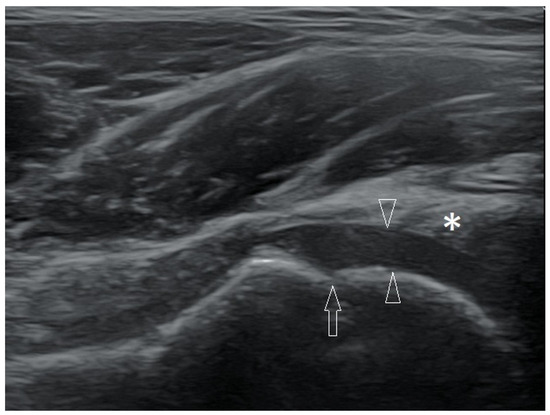

3.2.1. Osteochondritis Dissecans

3.2.2. Osgood–Schlatter Disease